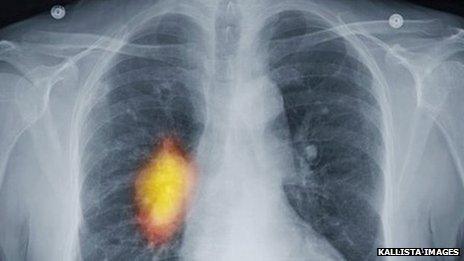

Older cancer patients 'should not be written off'

Older cancer patients should not be "written off" as too old for treatment, a charity has warned.

Macmillan Cancer Support said decisions on care should be made based on a patient's fitness, not their age.